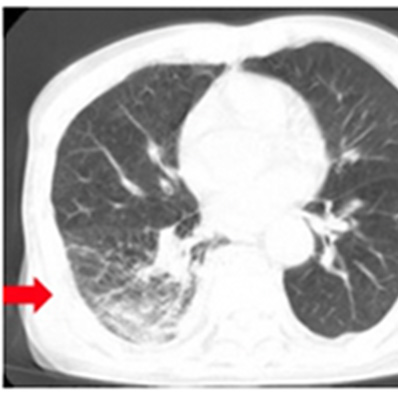

肺挫傷